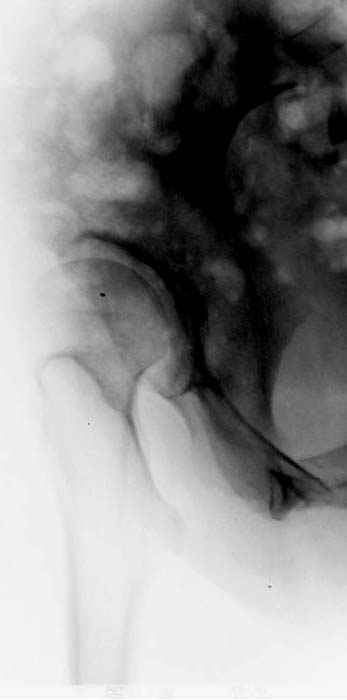

Модель несовершенна, согласен, однако я экспериментировал и с импровизированной илеофеморальной связкой и ацетабулярной губой. Результат был тот же, подвижный узел замыкался посредством аналога СГБ. Для интереса я прилагаю фото., где сымитированы наружные связки и вертлужная губа, но без СГБ видно по показаниям динамометра, что данные структуры незначительно только на 0.5 кг разгружают аналог отводящих мышц. Почему модель получилась именно такой можно рассказать и подробнее если захотите…